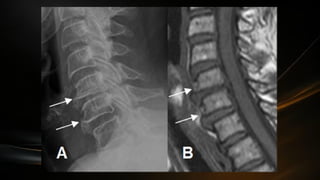

Medula espinal

• Parte del SNC ocupa el conducto vertebral protegida por las meninges

raquídeas

• Se extiende desde la articulación atlantooccipital hasta el borde

superior de la segunda vertebra lumbar (L2)

• En el extremo caudal la medula espinal termina en forma de cono

(cono medular) de esta porción sale el filum terminale que desciende

• La medula espinal en su trayecto muestra

dos engrosamientos fusiformes: las

intumescencias cervical y lumbrosacra

• La intumescencia cervical se extiende

desde la tercera vertebra cervical a la

segunda torácica

• La intumescencia lumbrosacra desde la

novena vertebra torácica hasta la primera

lumbar